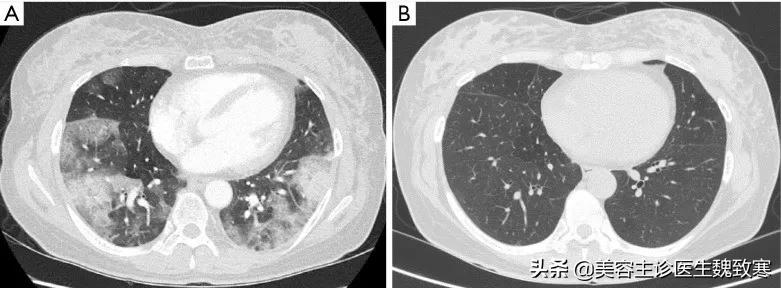

胸部CT表现为弥漫性GOS伴小叶间隔增厚和不规则胸膜下实变,无纵隔淋巴结肿大或胸腔积液 (见下图A) 。没有明确的证据显示肺血栓栓塞或右心室增大。

随后在门诊进行的胸部CT随访显示,先前的肺部病变完全痊愈 (见上图B) 。